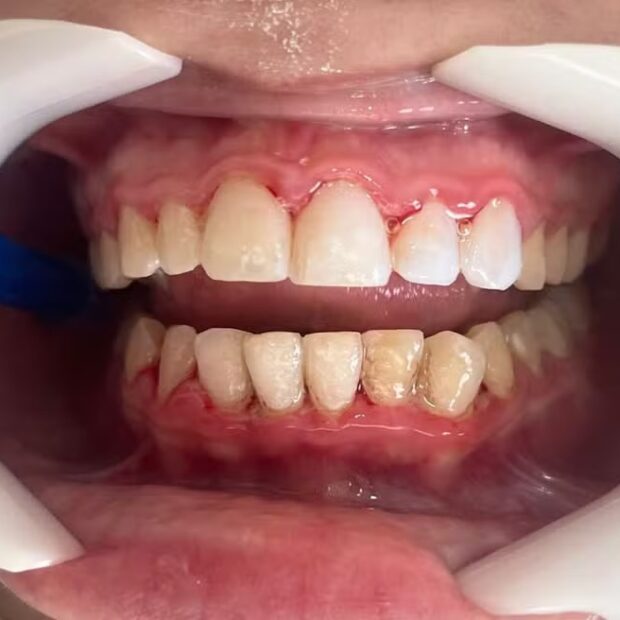

Após aplicar lentes dentárias, uma adolescente de 17 anos de São Vicente, no litoral de São Paulo, apresentou um quadro de necrose óssea e pulpar, que é a morte da polpa dentária, área do dente em que ficam vasos sanguíneos e terminações nervosas.

De acordo com o cirurgião-dentista Mayke Figueiredo, que assumiu o caso da adolescente, o procedimento provocou um quadro grave de periodontite. Foi então feita uma raspagem e se iniciou o tratamento medicamentoso.

“As facetas [lentes] estavam com infiltração e mal adaptadas, todas com degraus e excesso de resina, ocasionando uma periodontite, que é uma infecção gengival grave que danifica a gengiva e destrói o osso maxilar”, disse à Folha de S.Paulo.

Figueiredo acrescentou que a erosão dental deixa a dentina exposta, causando dor e sensibilidade. Ele afirma que a adolescente teve perda óssea e poderia ter perdido os dentes. Também correu o risco de que uma bactéria chegasse à sua corrente sanguínea.